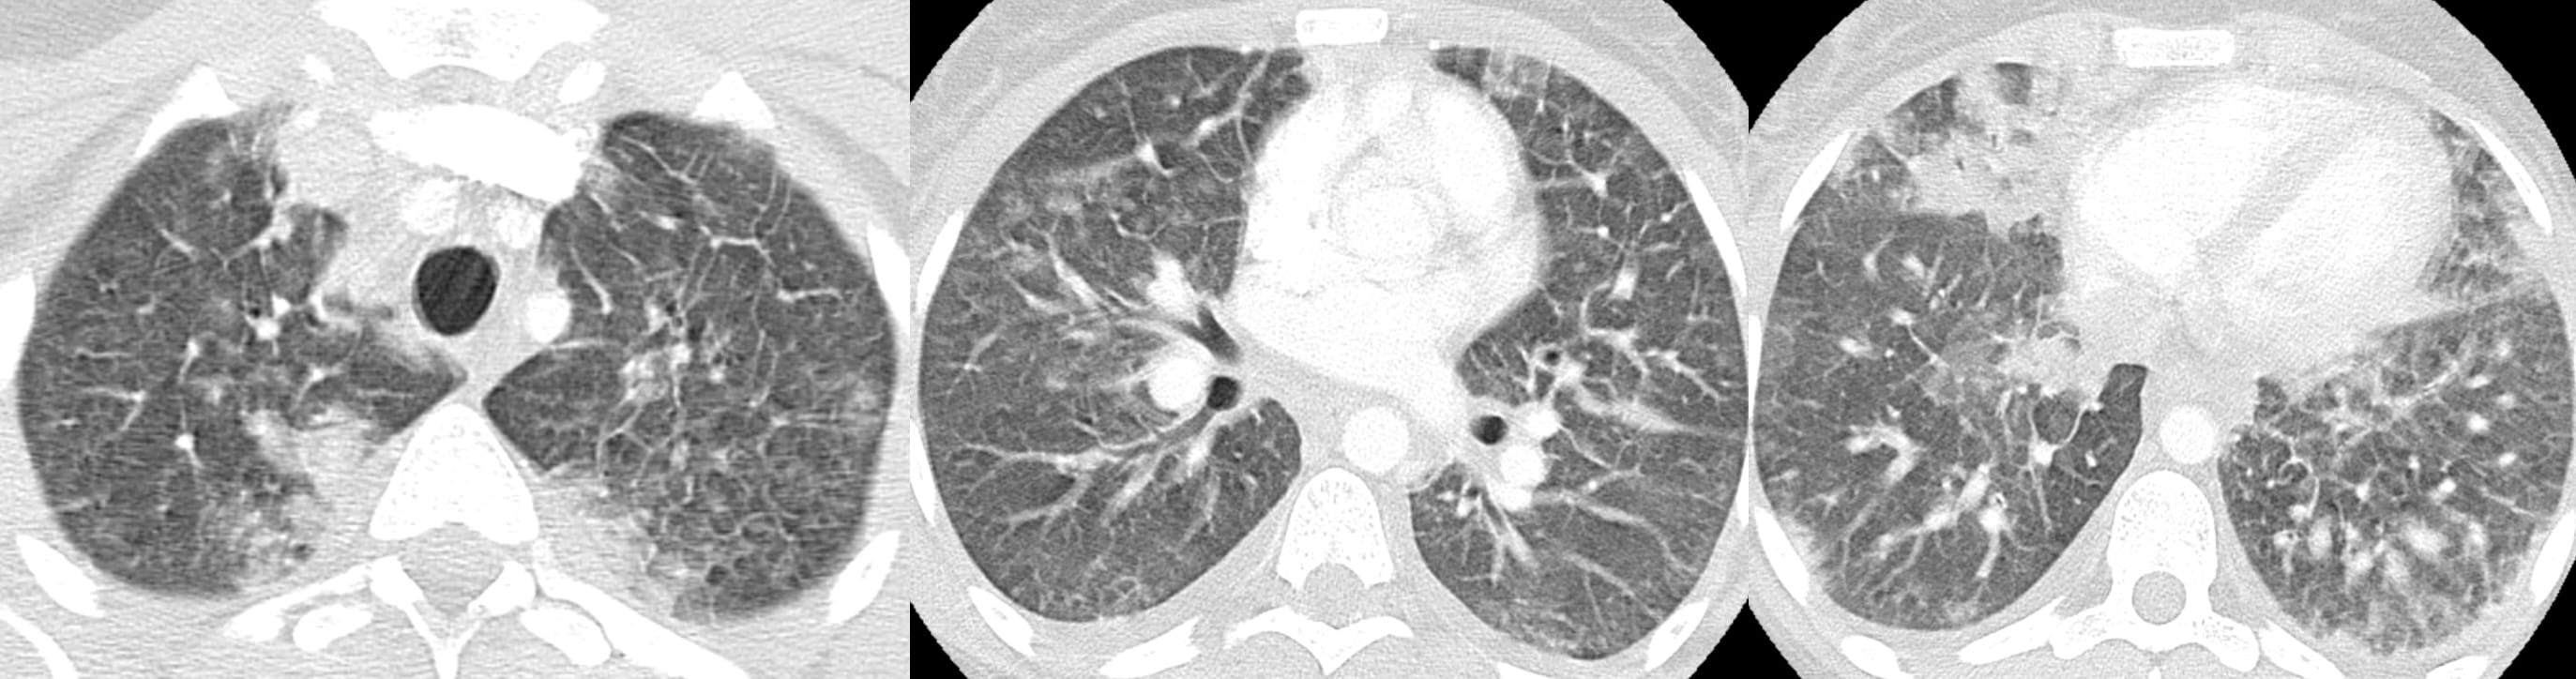

It’s a matter of how many I put there with my macrophage spray can…

Should we really discard DIP ?

• Alveolar [Smoker’s] Macrophage Pneumonia (AMP) replaces Desquamative Interstitial Pneumonia

Yes, we cannot tell how much of the opacity is SRIF versus Smoker’s Macrophages versus both!

“Findings of Smoker’s Lung are present in the form of: centrilobular emphysema in the upper lungs and patchy pulmonary ground glass opacities, consistent with accumulation of Smoker’s Macrophages and, possibly, Smoking-Related Interstitial Fibrosis.”